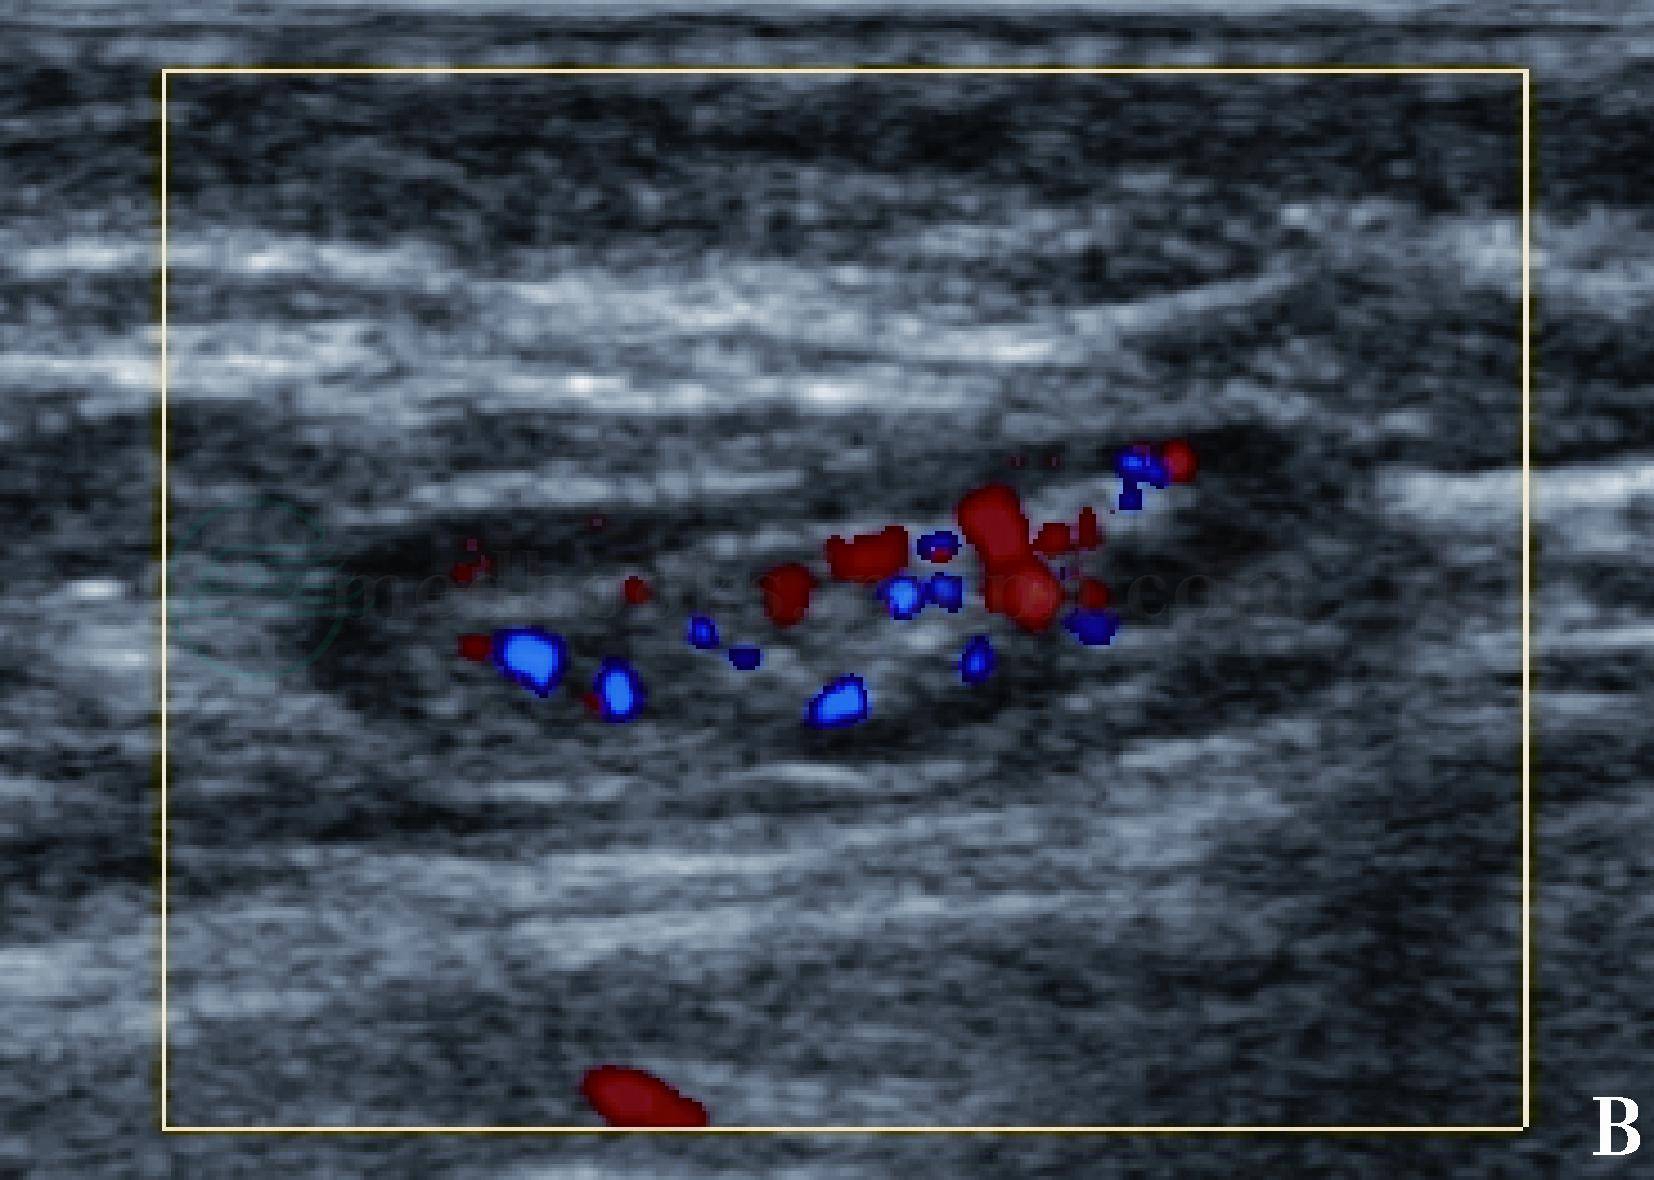

图3 正常腋下淋巴结声像图

彩色多普勒超声显示淋巴结髓质内散在点状血流